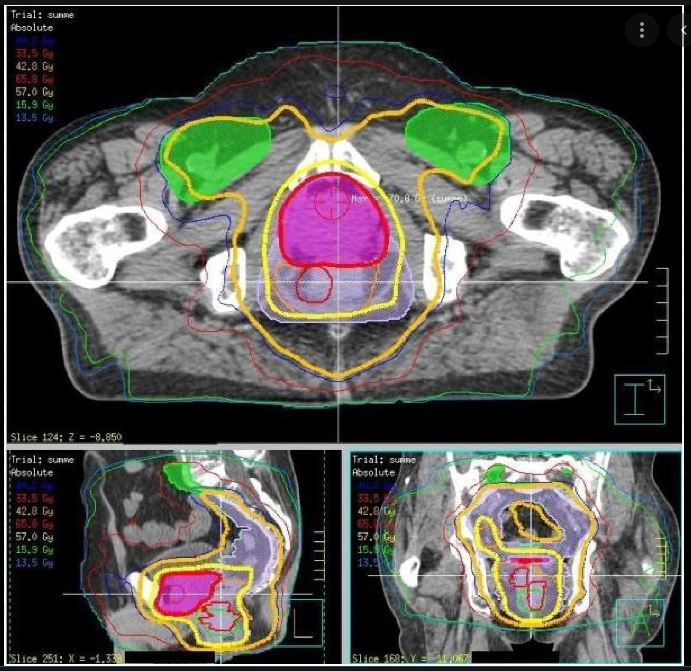

this is a

rotational treatment

what treatment type is this

IMRT

Which plan protects the OAR/small bowel the best

C